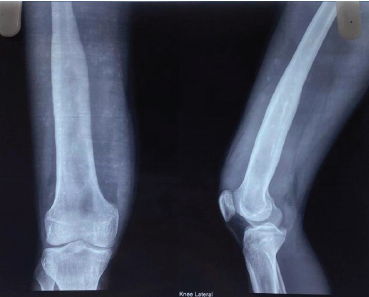

Acute Onset Common Peroneal Nerve Palsy Secondary to Fibular Head Osteochondroma in an Adolescent: A Case Report

Kevin Jain , Sandeep Patil , Stavan Amin , K S Akshay , Sanjeev Ghildiyal

………………………………p.185-188